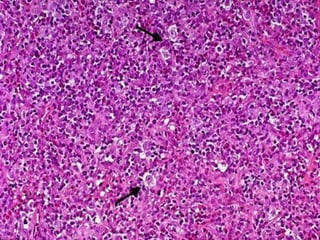

MIXED CELLULARITY

 Accounts for 20-25% of HL

MICROSCOPY

 Diffuse effacement of nodal architecture

 Heterogenous cellular infiltrate composed of small

lymphocytes, eosinophils, plasma cells &

macrophages

 Admixed with plentiful neoplastic cells – Classical

Reed-Sternberg cells & Mononuclear variants

 RS cells are CD 15 & CD 30 positive

 70% EBV positive

 More common in males

 Biphasic incidence – young adults &

>55yr

 Systemic symptoms – Night sweats &

weight loss

 Advanced tumor stage - 50% Stage 3

or 4

 Good prognosis

Mixed cellularity, CD15+ RS cells